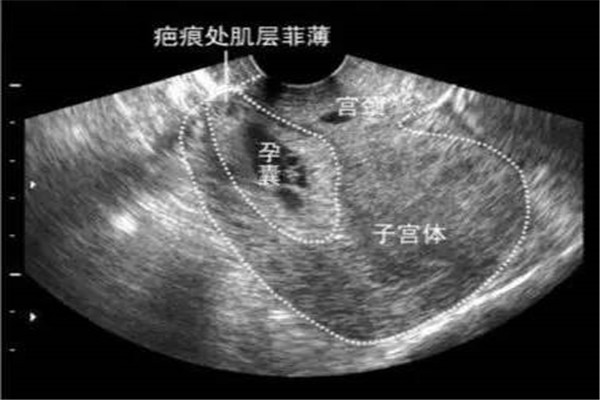

【一位怀孕35周的头胎妈妈张女士突然感到上腹部疼痛,一开始以为是胃疼,没想到疼痛加剧,这才被家人送到医院;医生初步怀疑张女士子宫破裂,但在随后的B超检查中,医生发现,胎儿的一条腿竟然进入到了腹腔,大腿根正卡在子宫壁上。

医院立即组织产科急救团队,第一时间实施手术,不到十分钟就将胎儿顺利剖出,母女平安。最后医生追问患者既往病史,才得知原来张女士在去年曾经做过子宫肌瘤剔除手术,在手术疤痕还未完全愈合的时候就怀孕了,这才导致了胎儿一脚“踢”破子宫。】

在妊娠晚期或临产时,有的产妇过去子宫有手术疤痕,也容易发生破裂。如剖宫产、子宫肌瘤剔除手术,在再次妊娠时,瘢痕组织经受不住子宫内容物的增加,可以自然破裂,也可以在宫缩时发生破裂,由于子宫破裂时十分危险的情况,严格的产前检查,确定恰当的分娩方式也是很重要的。